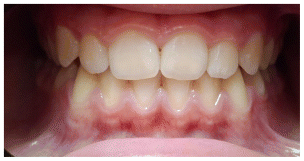

Case 2

The patient was a growing female child who presented during early mixed dentition with an anterior crossbite associated with a deep overbite and a marked sagittal discrepancy (Figures 12–19). The initial clinical examination revealed a negative overjet, complete anterior deep bite, and a functional Class III occlusal pattern. Extraoral assessment showed a flattened facial profile, while cephalometric analysis confirmed a skeletal imbalance characterized by increased SNA and SNB values, an ANB of 0°, negative Withs appraisal, and significant dentoalveolar compensations, including proclination of both upper and lower incisors (Table 3). The vertical pattern was predominantly hypodivergent, suggesting a high risk of unfavorable mandibular growth progression if left untreated. Given the patient’s young age and growth potential, an early interceptive treatment was planned to use the AMCOP® TC appliance, with the aim of correcting the anterior crossbite, improving neuromuscular balance, and guiding sagittal and vertical development during growth. The appliance was worn nightly and for additional daytime hours, according to patient compliance.

After 18 months of treatment, a clear clinical improvement was observed. Intraoral examination demonstrated complete correction of the anterior crossbite, with establishment of a positive overjet and normalization of the anterior occlusal relationship. The deep bite was reduced, allowing more functional anterior guidance. Occlusal relationships improved toward a stable dental Class I, and the need for excessive dentoalveolar compensation was reduced. Cephalometric reassessment showed an overall improvement in sagittal relationships and incisor inclinations, with a trend toward normalization of the previously altered parameters. These findings indicate that early functional therapy with the AMCOP® TC appliance was effective in intercepting the developing Class III malocclusion, improving occlusal function, and potentially reducing the severity of future skeletal discrepancies (Table 4).